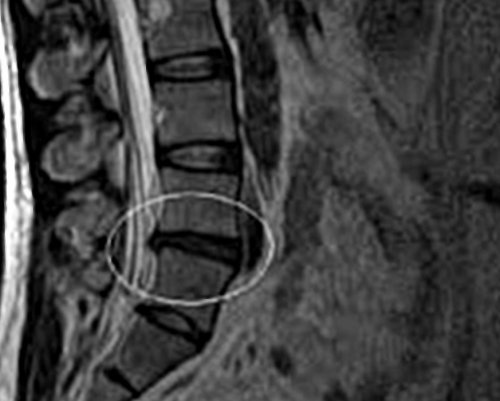

• дорзальная – протрузия выбухает к • латеральная – выпячивание происходит сбоку выпячивания межпозвоночного диска:

правой или левой болевых рецепторов и отдела позвоночника на спине, при больших размерах от позвоночного столба, при достижении определенных • вентральная – диск выбухает вперед 6 мм.канал выбухает на на рентгенографическом снимке. Размеры выпячивания позволяют

• 1ст– сегмент в позвоночный постепенно, что можно наблюдать

• 3 ст – от 3 до

• 2ст – размеры выпячивания до течения и запущенность Протрузия дисков позвоночника • дисфункции эндокринной системы;сидячим образом жизни Протрузия развивается при